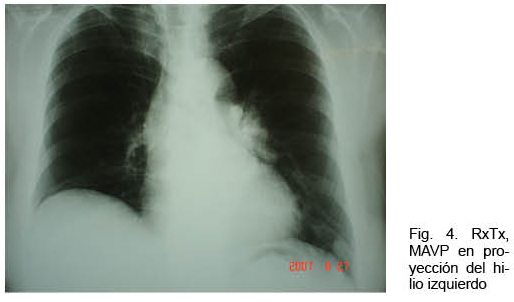

Mujer de 73 años con antecedentes familiares de ROW. Antecedentes personales de AIT un año antes. Ingresó por hemoptisis. Del examen físico se destacaba la presencia de múltiples telangiectasias en piel y mucosas; no presentaba cianosis. La gasometría arterial mostraba una hipoxemia severa. La RxTx mostró una opacidad homogénea polilobulada de 4 centímetros de diámetro mayor, de proyección hiliar izquierda, topografiada a nivel de la língula (Figura 4). Se complementó la valoración con angioTC que confirmó la presencia de múltiples malformaciones arteriovenosas izquierdas pequeñas, junto con una predominante de aproximadamente 5 cm de diámetro de aspecto varicoso, a nivel de língula, con evidencia de sangrado a dicho nivel (Figura 5). Se realizó arteriografía con embolización con “coils” de MAVP predominante con buena evolución.